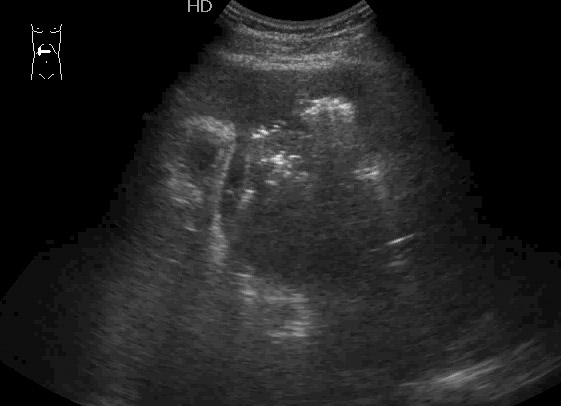

#6

Пожилой мужчина, мы ему уже дренировали абсцесс левой доли печени как минимум полгода назад.

Опять температура, симптомы интоксикации.

В левой доле определяется один крупный и несколько мелких абсцессов.

Больший абсцесс задренирован, мелкие раздренировались самостоятельно в бОльший.

У него же, по-видимому, мелкие протоковые конкрменты: